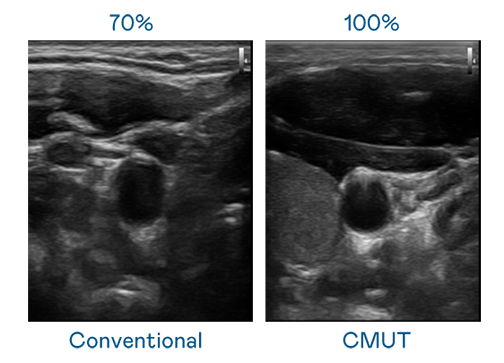

CMUT 技术是一种用电容式微机电元件来产生超音波讯号的技术。与传统 PZT 压电式技术相比,CMUT 频宽增加 30%,更宽频的超音波讯号让影像解析度大幅提升,是实现高影像品质医疗超音波扫描、促进精准医疗发展的关键技术。

大频宽带来超清晰影像

超音波影像的解析度高低,首先取决于探头能发出的讯号频宽。2121非凡 CMUT 可提供高清晰的超音波讯号,提供高频宽、高灵敏度、影像纹理细节更高的超音波影像,协助医护人员缩短影像判读时间及利用精准的医疗影像进行诊断。